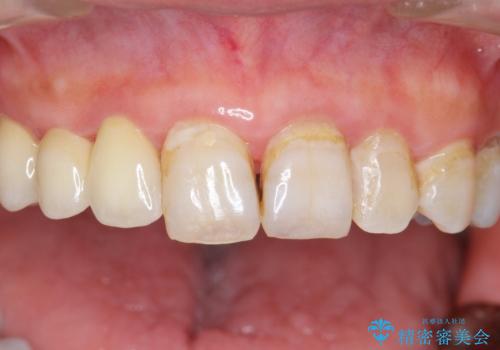

- 被せ物がかけてしまったことを主訴に来院された患者様です。

口腔内を精査したところ、右上のブリッジの内側(口蓋側)がかけており、下の前歯(右下1)には唇舌側に瘻孔を伴う大きな根尖病変ができていました。

右上のブリッジ(右上④3②)のやりかえと、下の前歯(右下1)の根管治療を行った後セラミッククラウンによる補綴治療を行いました。